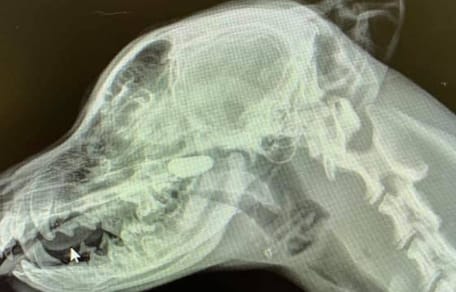

Une fois ramené dans le refuge, le chien a eu droit à un examen vétérinaire complet afin de vérifier son état de santé. Fort heureusement, il était bon. Mais cela aurait pu être différent car le chien était en plein soleil.